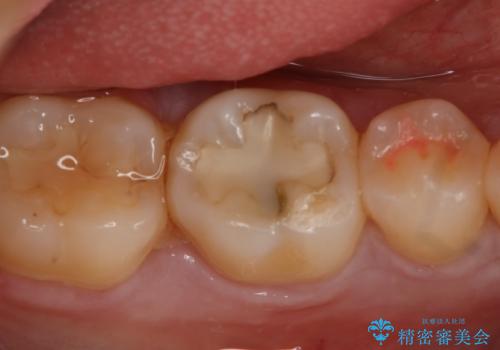

詰め物が外れかけてるのでやり替えたい セラミックインレー修復・フルジルコニアクラウン